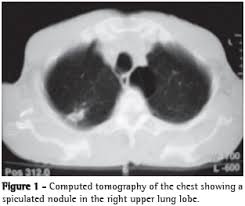

A síndrome miastênica de Lambert-Eaton é uma doença auto-imune caracterizada por fraqueza e fadiga dos músculos proximais, particularmente da cintura pélvica, extremidades inferiores, tronco e cintura escapular. Há uma preservação relativa dos músculos extra-ocular e bulbar. O carcinoma de células pequenas do pulmão é uma condição freqüentemente associada, embora outras doenças malignas e auto-imunes possam estar associadas.